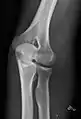

- Knee - AP and Lateral. Intra Condular projections on request

Right knee, anteroposterior

Right knee, lateral

Patella, (slightly skew) skyline